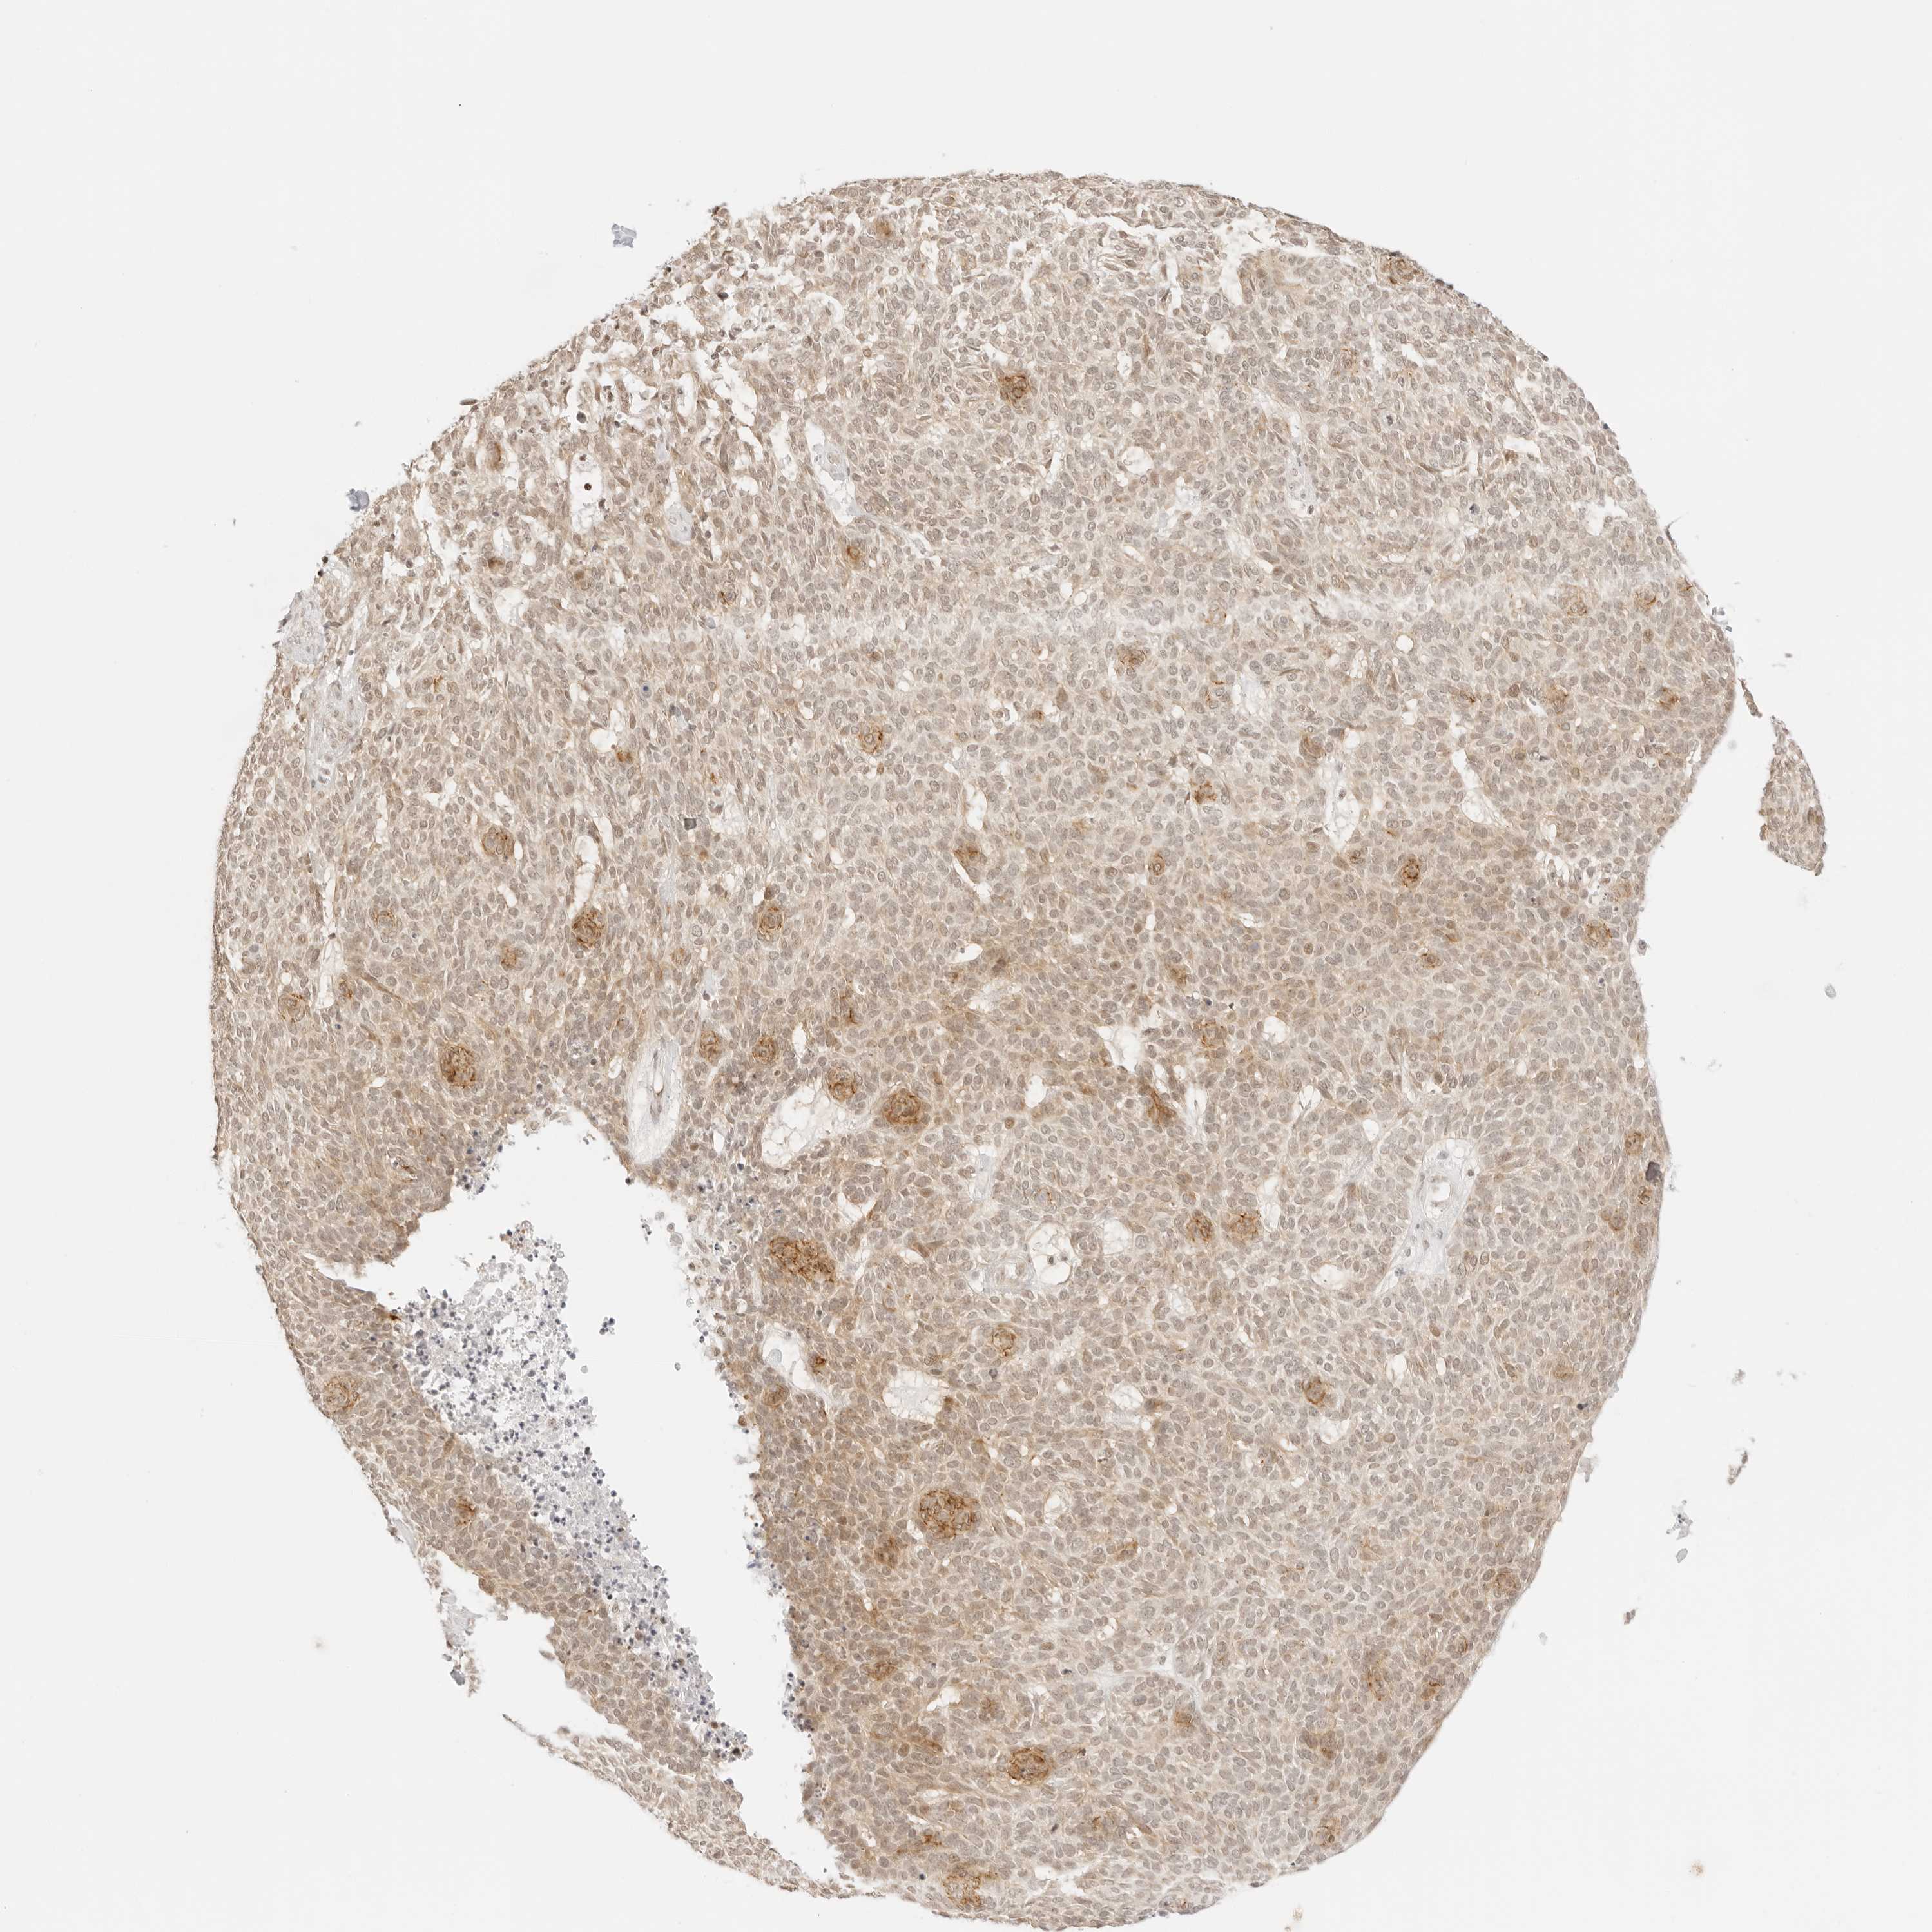

SKIN CANCER - Protein expressioni

A mouse-over function shows sample information and annotation data. Click on an image to view it in a full screen mode. Samples can be filtered based on level of antibody staining by selecting one or several of the following categories: high, medium, low and not detected. The assay and annotation is described here.

Each image is clickable and will lead to virtual microscopy that enables deeper exploration of all samples and also displays staining intensity scores, fraction scores and subcellular localization as well as patient and tissue information for each sample.

Antibody HPA027478

Squamous cell carcinoma, NOS